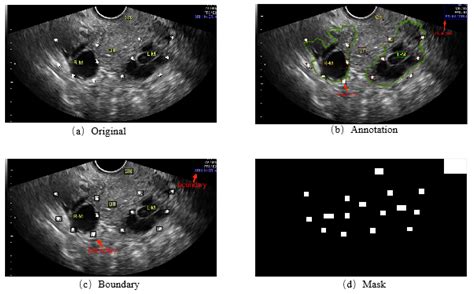

An ultrasound, or sonogram, uses high-frequency sound waves to create images of the internal structures of the body. When specifically looking for markers associated with ovarian health, doctors utilize this technology to examine the size, shape, and structure of the ovaries. Because ovarian cancer is often asymptomatic in its early stages, imaging tools play a critical role in detecting abnormalities such as cysts, solid masses, or enlarged ovaries that may warrant further investigation.

It is important to understand that an ultrasound alone cannot definitively diagnose ovarian cancer. Instead, it serves as a screening and diagnostic tool that helps specialists categorize ovarian masses as either benign (non-cancerous) or suspicious. By analyzing the characteristics of a mass, such as its internal composition, blood flow, and the presence of irregular borders, radiologists can determine the likelihood of malignancy.

When a radiologist or sonographer performs an ovarian cancer ultrasound, they are looking for specific morphological patterns. A normal ovary usually has a smooth, consistent texture. When potential malignancy is suspected, the following "red flags" may be noted: